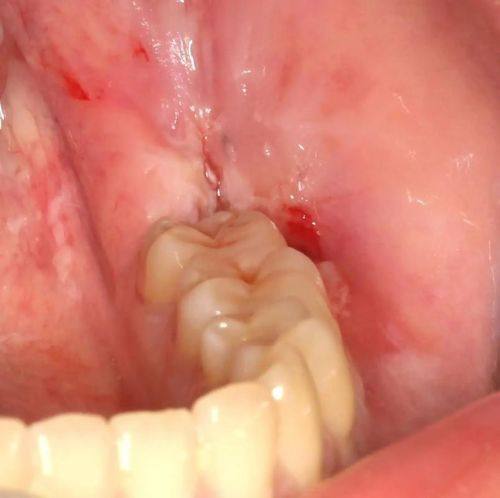

智齿拔除:可开展切牙龈拔智齿、完全性骨埋伏阻生牙拔除等复杂智齿项目,搭配口腔CT定位保护诊疗安心。

笑研口腔门诊部完全性骨埋伏阻生牙拔除:1580元起